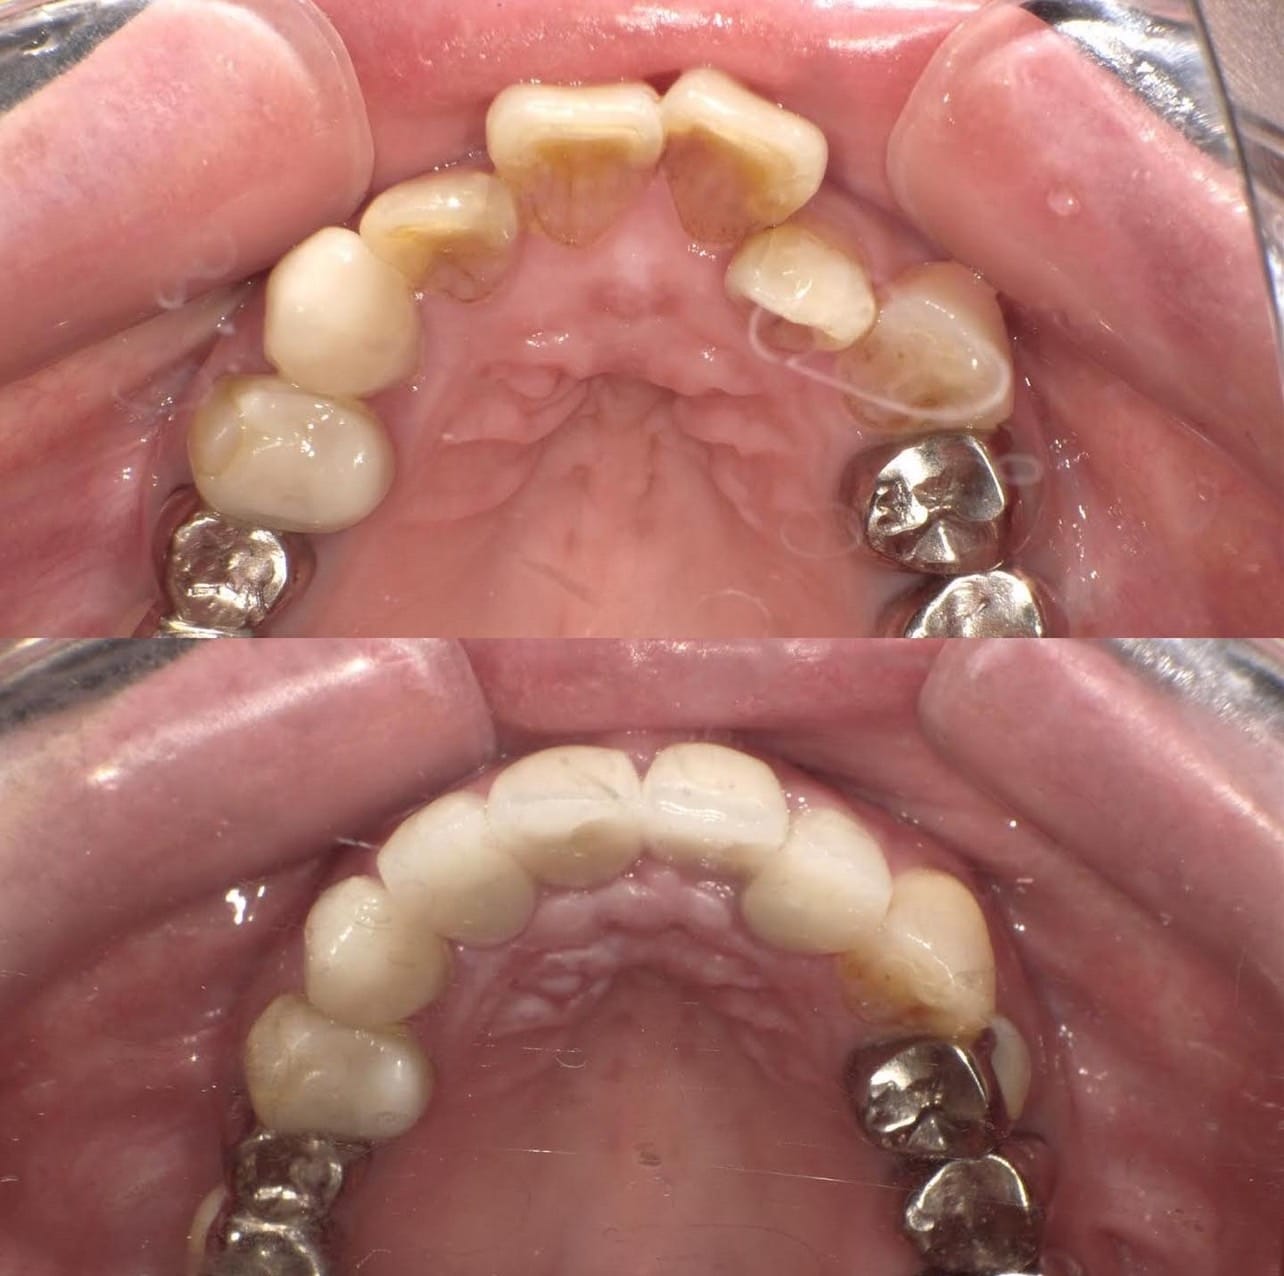

Case022 – インプラント

広島からの患者様です。

前歯を綺麗にしたい。インプラントをしたい。

という主訴で東京の歯医者をいろいろ調べて当院を選んでくださいました。

毎回、遠い中しっかり通ってくださり、選んで頂けた嬉しさと、その気持ちに応えたいという想いで診療させて頂きました。

前歯はご希望のお色でラミネートベニアでは出せない透明感のあるセラミックに上下左側7はインプラントをさせて頂きました。

左上は破折で温存不可。

骨も少なかったので、サイナスリフトも行い計五回の来院で被せ物を入れさせて頂きました。

左下は前回のクリニックでの埋入位置が深すぎて食べカスも毎回詰まる、セルフメンテナンスではら汚れも取れない。インプラント周囲炎にもなっていたので、一度前のインプラントを除去し、そこから新しくインプラントを埋入し、診療させて頂きました。